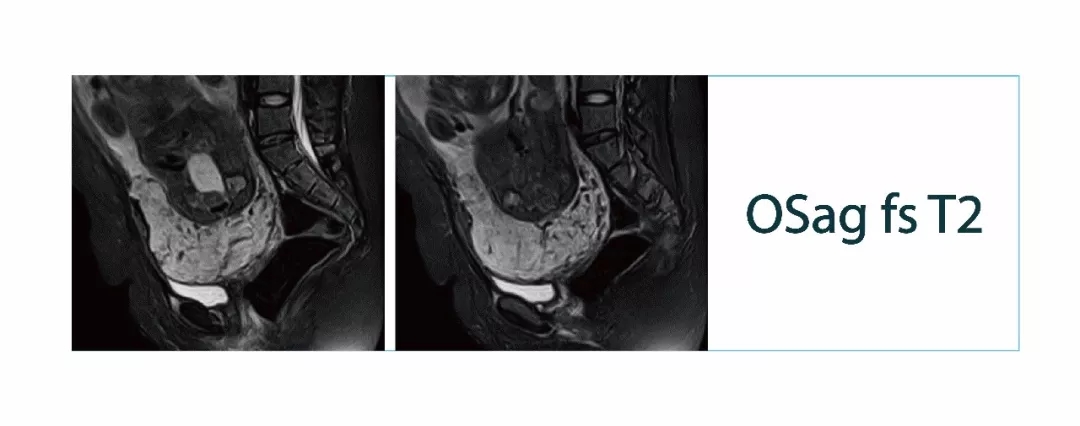

【朗润影像档案】磁共振影像病例分享(编号20180302)